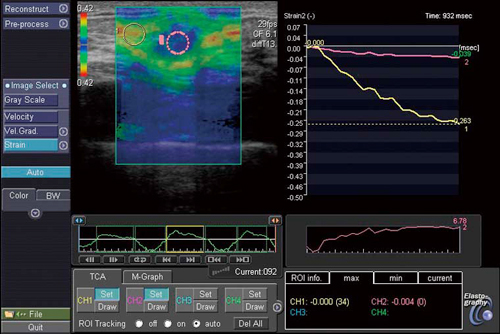

●Elastography(図3)

プローブを軽く圧迫・解放することで,病変部位の硬さ(弾性)を映像化します。圧迫による組織の動きをグラフ化することで,圧迫の与え方が適正かどうかの確認ができ,RAWデータを用いた独自の解析機能と合わせて定量的な解析が可能です。

図3 Elastography